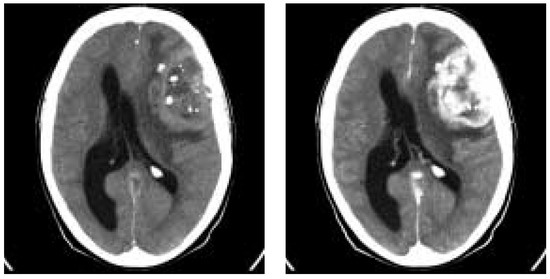

The impact of CT in acute cerebral ischaemia

by Rüdiger von Kummer

Swiss Arch. Neurol. Psychiatry Psychother. 2004, 155(7), 315; https://doi.org/10.4414/sanp.2004.01528 - 1 Jan 2004

Computed tomography (CT) including CT perfusion imaging and CT angiography has the capacity to assess stroke pathology on a functional and morphological level and can thus provide important information about patients with acute stroke. It excludes brain haemorrhage, assesses the extent of perfusion [...] Read more.

Computed tomography (CT) including CT perfusion imaging and CT angiography has the capacity to assess stroke pathology on a functional and morphological level and can thus provide important information about patients with acute stroke. It excludes brain haemorrhage, assesses the extent of perfusion deficit, the extent of ischaemic damage, and the site and type of arterial obstruction. In patients with transient or mild symptoms, the assessment of vascular pathology and consecutive haemodynamic impairment is most important to guide treatment that will prevent disabling stroke. In patients with completed stroke, the early assessment of ischaemic damage is most important. Ischaemic brain tissue below the blood flow level of structural integrity takes up water immediately that causes a decrease in X-ray attenuation. Computed tomography has thus the specific advantage to identify the brain tissue that is irreversibly injured. If CT can exclude major ischaemic damage in acute stroke patients, reperfusion strategies may rescue brain function even after accepted therapeutic time windows. Full article